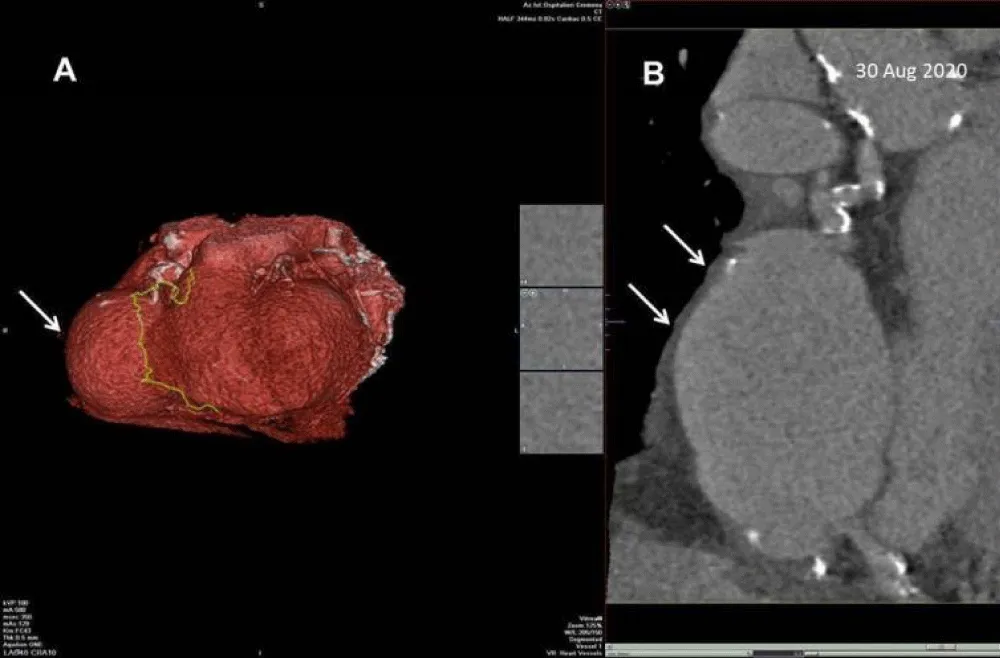

According to these echocardiographic findings, we supposed a giant coronary aneurysm. To confirm our suspicion the patient underwent Coronary Computed Tomography Angiography (CCTA) with 3D reconstruction that showed a giant aneurysm of the right coronary artery at mid-level, preceded by a mild aneurysm of the proximal tract (Figure 4a,4b). CCTA showed also two small aneurysms of the circumflex artery and diffuse atherosclerosis diseases with significant stenosis on the mid-left anterior descending artery (LAD). It was also reported significant calcification of coronary arteries (Calcium score = 3837 Agatston).

Figure 4: (a) Coronary Computed Tomography Angiography (CCTA) with 3D reconstruction. (b) CCTA with multiplanar reconstruction. Both show a giant aneurysm of the right coronary artery at mid-level (white arrow).